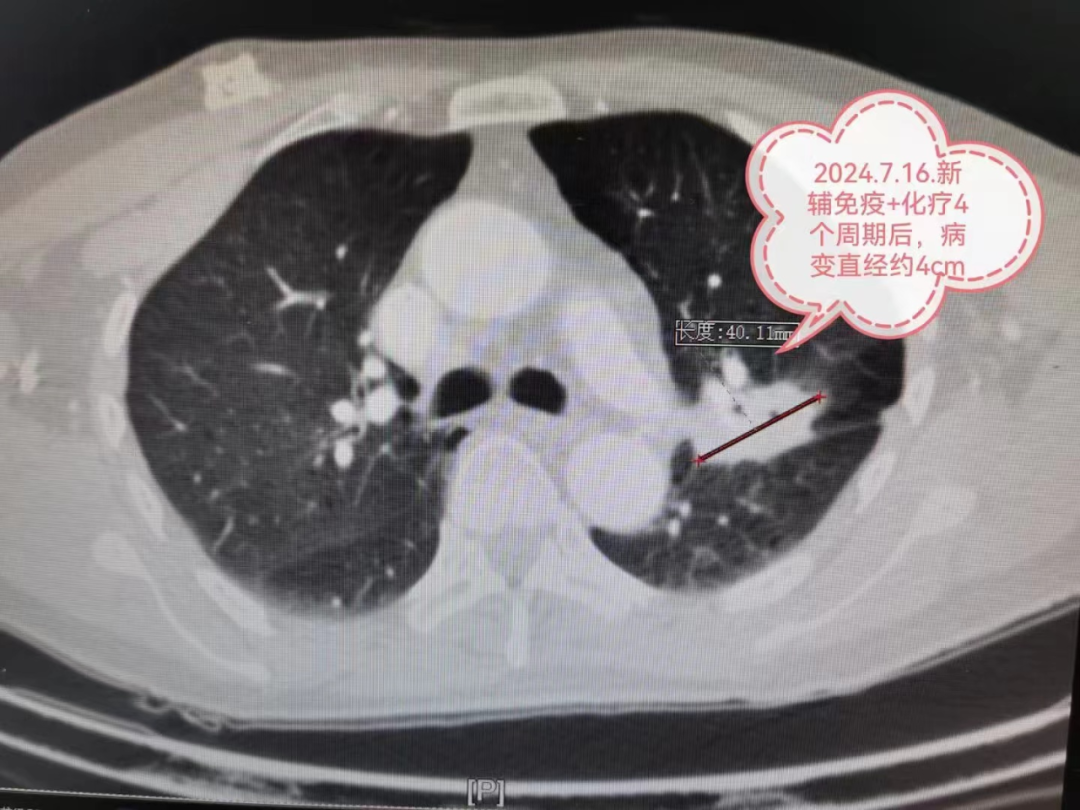

肺癌是我国发病率和病死率最高的恶性肿瘤,其中非小细胞肺癌约占肺癌的80%-85%。肺癌的治疗原则是以外科手术为首选的综合性治疗,所以,外科手术是治疗肺癌的首选方法。早期肺癌并行根治性手术,5年生存率可达90%以上。然而约60%的肺癌临床确诊时已处于局部晚期或转移性晚期,错失了手术治疗的时机,既往只能采用放射治疗(放疗)或化学药物治疗(化疗)及联合放化疗的治疗方式,但效果并不理想。 近年来由于基因靶向治疗、免疫治疗等先进治疗手段的出现,术前新辅助治疗在偏晚期肺癌的治疗中取得了很好的疗效,偏晚期肺癌得到降期而获得手术机会。下面,我们来看一个实际的例子: 今年2月严先生因 “ 反复咳嗽、咳痰3年, 病情加重伴气促2月” 到贵州航天医院就诊, 经胸部CT检查发现左肺上叶占位, 肺穿刺病理确诊为左上肺鳞癌, 肿瘤大小约为66mm×77mm, 且肿瘤包裹左上肺重要血管。 贵州航天医院肺癌MDT(多学科会诊)团队开会讨论,考虑肺癌分期较晚,暂无手术机会,决定先给予3-4个周期的新辅助化疗+免疫治疗后,再判断有无手术机会。 经过4个周期的新辅助化疗联合免疫抑制治疗后,肿瘤最大直径由77mm明显缩小到40mm,分期由IIIA期降为IIA期。 心胸外科陈光春主任团队召开病例讨论会,大家一致认为新辅助化疗联合免疫抑制治疗效果明显,患者获得了根治性手术机会。经过严谨、全面的术前准备后,最终为严先生成功实施单孔胸腔镜下肺癌根治术,手术圆满成功。 术后5天,严先生已恢复日常生活能力,严先生及其家人感叹术前的4个周期化疗+免疫治疗加上单孔胸腔镜微创手术,最终让“心里一颗大石头放下了”。 术后病理检查显示:经过之前的新辅助治疗,病变的大小由77mm缩小到40mm(缩小约48%),经过显微镜观察,实际的癌细胞仅仅残存6%,也就是说40mm肿块里面94%的组织已经没有癌细胞啦,医学上称这种情况叫做主要病理学缓解(MPR)。 有研究显示经过新辅助治疗,约50%甚至更多患者可以达到主要病理学缓解(MPR)。如果新辅助治疗后病理检查提示病灶已经没有癌细胞了,称之为完全病理学缓解(PCR)。 写到这里,可能大家会有些疑问,我们来总结回答一下: 什么是辅助治疗? 辅助治疗是指术后继续使用化疗、放疗、靶向、免疫等手段巩固治疗,降低复发可能性。但并不是所有患者都需要进行辅助治疗,需依据患者的术后病理确定,如肺腺癌的患者,手术后确定是病理类型良好的Ⅰa期,则术后定期随访观察即可,一般无需进行辅助治疗。 什么是新辅助治疗? 新辅助治疗是指术前接受化疗、放疗、靶向、免疫等治疗手段,使得肿瘤变小,实现降期,使得患者获得手术机会,并获得更好的效果。术前免疫治疗还可能通过免疫作用清除微转移灶,从而实现预防肿瘤复发转移的作用。 新辅助治疗具有两大优势:一方面,对于部分没有手术机会的患者,通过新辅助治疗获得手术机会,降低手术难度和风险,提高手术根治率;通过缩瘤减少手术的切除范围,提高患者术后生活质量;另一方面,通过新辅助治疗消灭常规影像学检查不能测到的微小转移灶,降低术后复发及远处转移的可能。例如:存在腋窝淋巴结转移的乳腺癌患者,直接手术复发风险较高,可先进行6个周期的新辅助化疗或者新辅助化疗联合靶向治疗,然后再手术,此时效果相对较好且复发风险较低。 为什么过去的晚期肺癌 不做手术? 在过去,没有基因靶向治疗和免疫治疗,只有化疗、放疗。放化疗的抗肿瘤作用比较有限而副作用又比较大。副作用大,能够使用时间就短,更多疗程的术前放化疗病人是无法耐受的。本来效果就有限,然后病人能够承受的治疗疗程又特别短,这种情况下术前放化疗很难达到满足手术要求的疗效(比如:肿瘤缩小到被肿瘤包裹的血管能够在手术时暴露处理),所以在那个年代,晚期肺癌是做不了手术的。 为什么现在的晚期肺癌 有机会手术了? 新出现的基因靶向治疗和免疫治疗特点:副作用小,患者才可以长期使用;药物有效率高,使用以后肿瘤就容易变小甚至消失。所以,基因靶向治疗和免疫治疗以更高效的速率杀灭肿瘤细胞,原本一个非常广泛发展的肿瘤,可以被安全地缩小到一定程度范围,而且还不会伤及身体的根本。 手术不再是晚期患者不可企及的奢望,而是顺其自然地照进了现实。比如本文中的IIIA期肺癌患者,且肿瘤包裹左上肺重要血管,几乎没有手术机会,或者被迫切除左全肺,术后生活质量差。在免疫药+化疗药的协同作用下,肿瘤直径缩小48%,分期由IIIA期降为IIA期,于是手术机会来了,而且只切除了左上肺,保留住了左下肺,术后生活质量相对切除左全肺更好。手术切除后肿瘤残余比例不足10%,实现了主要病理缓解(MPR)。 贵州航天医院心胸外科简介 心胸外科是诊治疾病种类较为复杂,专科性非常强的一门学科。心胸外科手术难度大,风险高,对设备和配套要求也高,大众对心胸外科经常会存有误解,误认为心胸外科只是看胸外面的病,这就很容易让人联想到乳腺疾病等,其实胸外科主要看的是胸腔内的病,主要是食管、气管及肺上的疾病。如食管囊肿、食管平滑肌瘤、贲门失迟缓症、严重的反流性食管炎、食管裂孔疝、自发性食管破裂、食管、气管瘘、食管癌、食管胃交界处癌(贲门癌)、肺大疱(有时破裂引起自发性气胸)、肺脓肿、肺隔离症、肺结核球、肺结节等需到心胸外科就诊。 心胸外科导航 贵州航天医院呼吸综合楼003诊室 住院病区:呼吸综合楼4楼 门诊坐诊时间 每周一至周五每周一至周五 (08:00—12:00;14:00—17:00) 咨询电话 住院病区咨询电话:27677360(医生办公室);0851-27677732(护士站) 心胸外科专家 注:部分图片来源于网络,如有侵权,请联系删除。 供 稿:陈光春(心胸外科) 编 辑:唐语蔚 一 审:陈光春 二 审:陈 伟 三 审:蒙昌耀